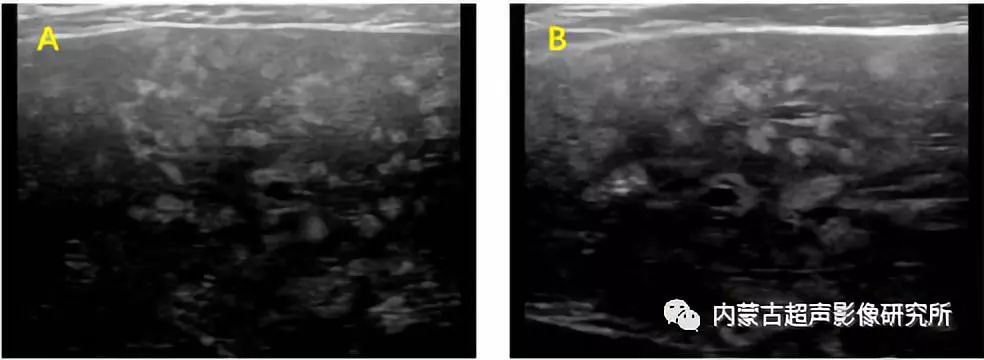

图1.胆道错构瘤(VMC)伴有弥漫性高回声病变和微囊 A: 肝脏解剖图 B:HE染色病理切片

VMC的超声表现为多发的不规则厚壁小囊性病变,其边缘不如肝囊肿锐利、光整、清晰(图2)。有少数超声上仅表现为肝实质回事弥漫性增粗,则可能因为囊性病变过于弥漫及微小,常规凸阵探头难以显示,仅表现为肝实质回声的不均匀,更换使用线阵探头提高分辨率,则有可能显示微小的囊性结构(图3)。

图3.胆道错构瘤(VMC)伴有弥漫性高回声病变和微囊的超声声像图(线阵探头,5-12 MHz)